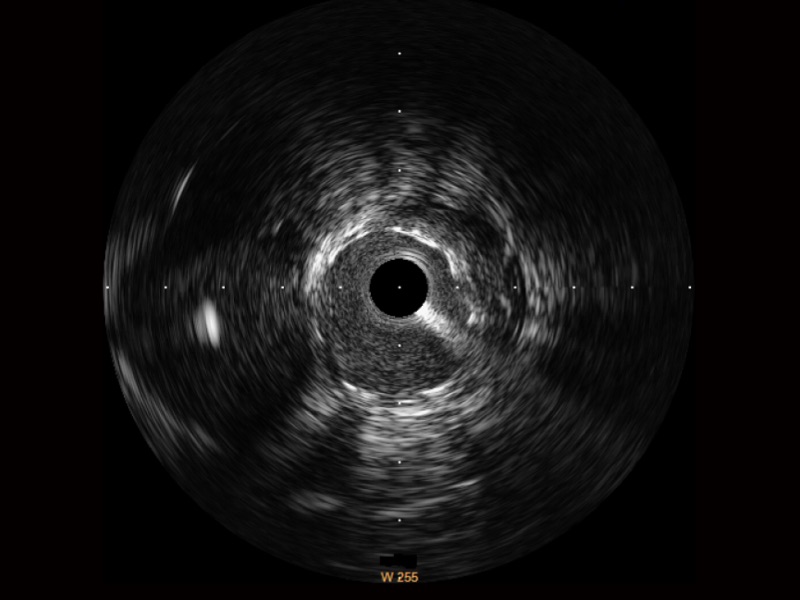

• 竞技宝(JJB)官方网站宽频IVUS图像

对比传统IVUS导管成像,竞技宝(JJB)官方网站宽频IVUS图像的近场支架梁显影更细腻,远场中膜外血管仍清晰可辨,兼顾远中近,兼顾分辨力与穿透深度